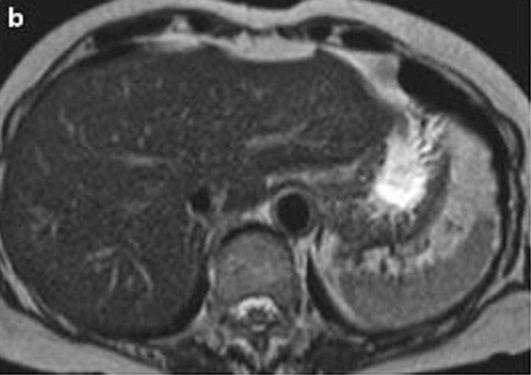

Image IRM de steatose fu foie

: Image de

hyperintense sur T1 et hypointense surT2 . L'infiltration graisseuse du foie provoque une diminution de

l'attenuation du parenchyme du foie . Sur le foie normale le

signal du parenchyme hepatique est similaire sur toutes les

images "in phase " et "opposed phase " . Dans steatose du

foie le signal du foie est hyperintense relative avec la rate (

T1 in phase ) et a opposed-phase , par la chute de

signal , image du foie est hypointensite ,

Steatose du foie : en phase .

Image IRM du foie |

|

Steatose du foie : Op de phase . |